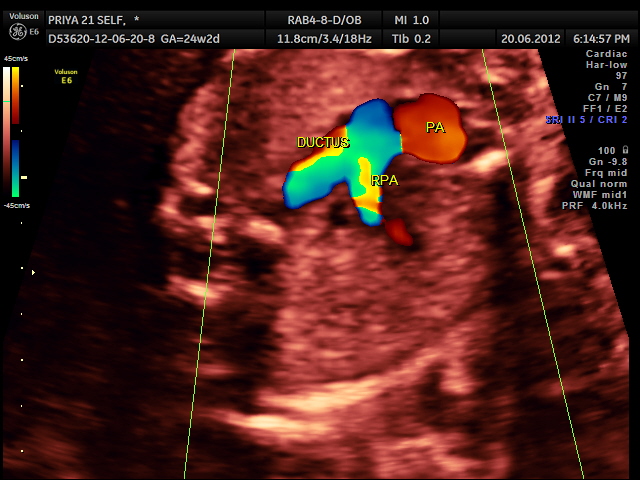

RV outflow tract with dilated Pulmonary trunk dividing into the Rt Pulm artery and the ductus seen. Aorta is not made out. ; SVC is seen

- The aortic valve, which separates the left ventricle and the aorta, is too small or completely closed (atretic).